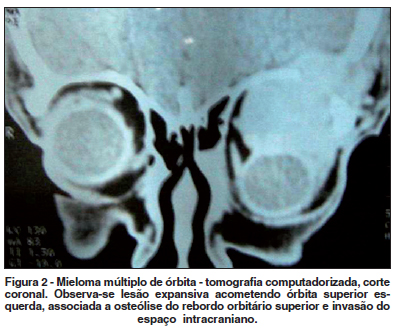

Tomografia computadorizada (TC) de órbita evidenciou lesão expansiva na região superior da órbita esquerda associada a lesões líticas do rebordo orbitário, com intensa captação de contraste (Figura 2). Radiografia de coluna vertebral evidenciou colapso parcial do corpo vertebral em L2.